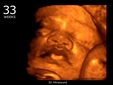

• 33. Hafta: Fetüs, 46 cm uzunluğundadır. Anne adayı, doğum belirtilerini hissedebilir.

33 Haftalık Gebelik